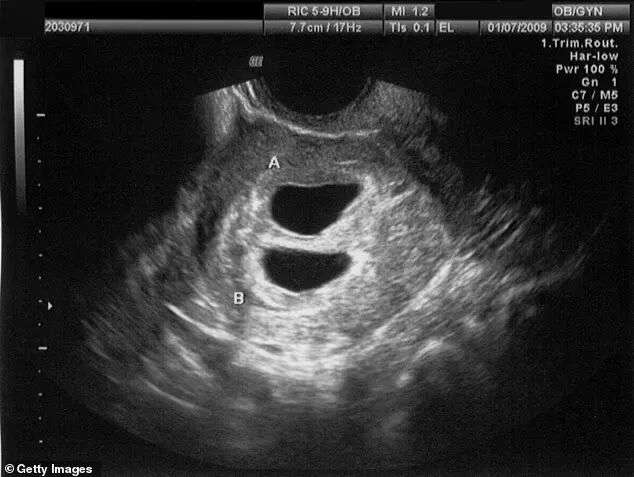

在经历过一系列检查流程后,医生决定采用“自然方案”,根据Courteney的排卵时间安排胚胎移植,过程还蛮顺利,最终她成功怀上了一对双胞胎。

之后她安心养胎,可在第11周产检时,医生却告诉了她一个不可思议的消息 —— 其中一个婴儿,其实是她和她丈夫的亲生孩子……

(其中一个是Courteney和她丈夫亲生的)

直到第11周去产检时,医生注意到两个胎儿不像同卵双胞胎,等16周产检时更加确认了这一点,因为两个胎儿的性别不同。

单个胚胎如果分裂,只会产生基因完全一致的同卵双胞胎,两个孩子性别不同,就证明他们并非来自同一胚胎,其中一个只能是Courteney的。

不过已经排除了这种可能,医生检查过她的卵泡和黄体,确认她只排了一颗卵子,同样无法形成两个性别不同的孩子。至于一些极端的染色体缺失、变异或者患病现象,目前也暂未发现。